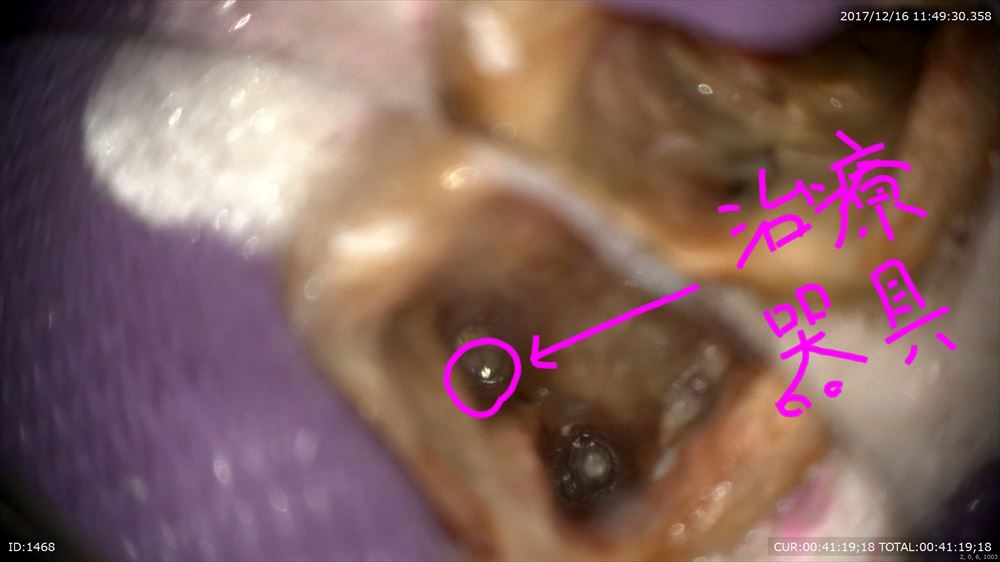

他院で行って治らない原因が

「治療器具」

歯科ドックで根管の中に治療器具の取り残しが見つかったケースです。

本日感染源であるガッタパーチャを除去し、ようやく器具にたどり着きました。

次回で何とか取りたいです!!マイクロスコープ治療でしか不可能な世界です。